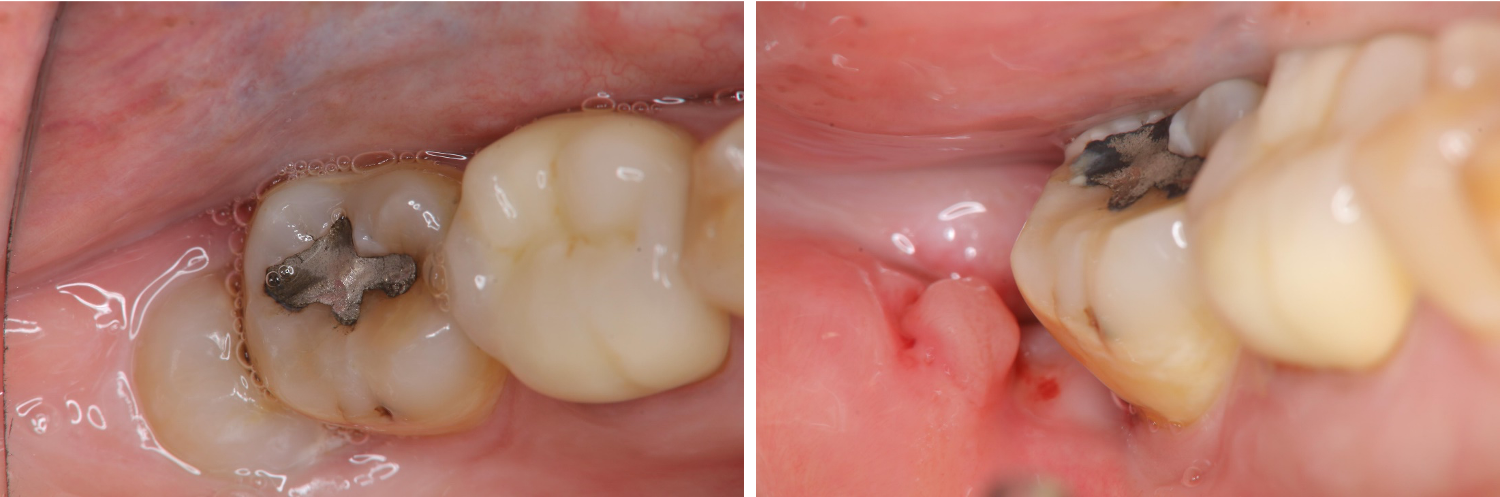

拔牙後傷口處理-阻生齒蛀牙-#48

口腔外科

拔牙後傷口處理